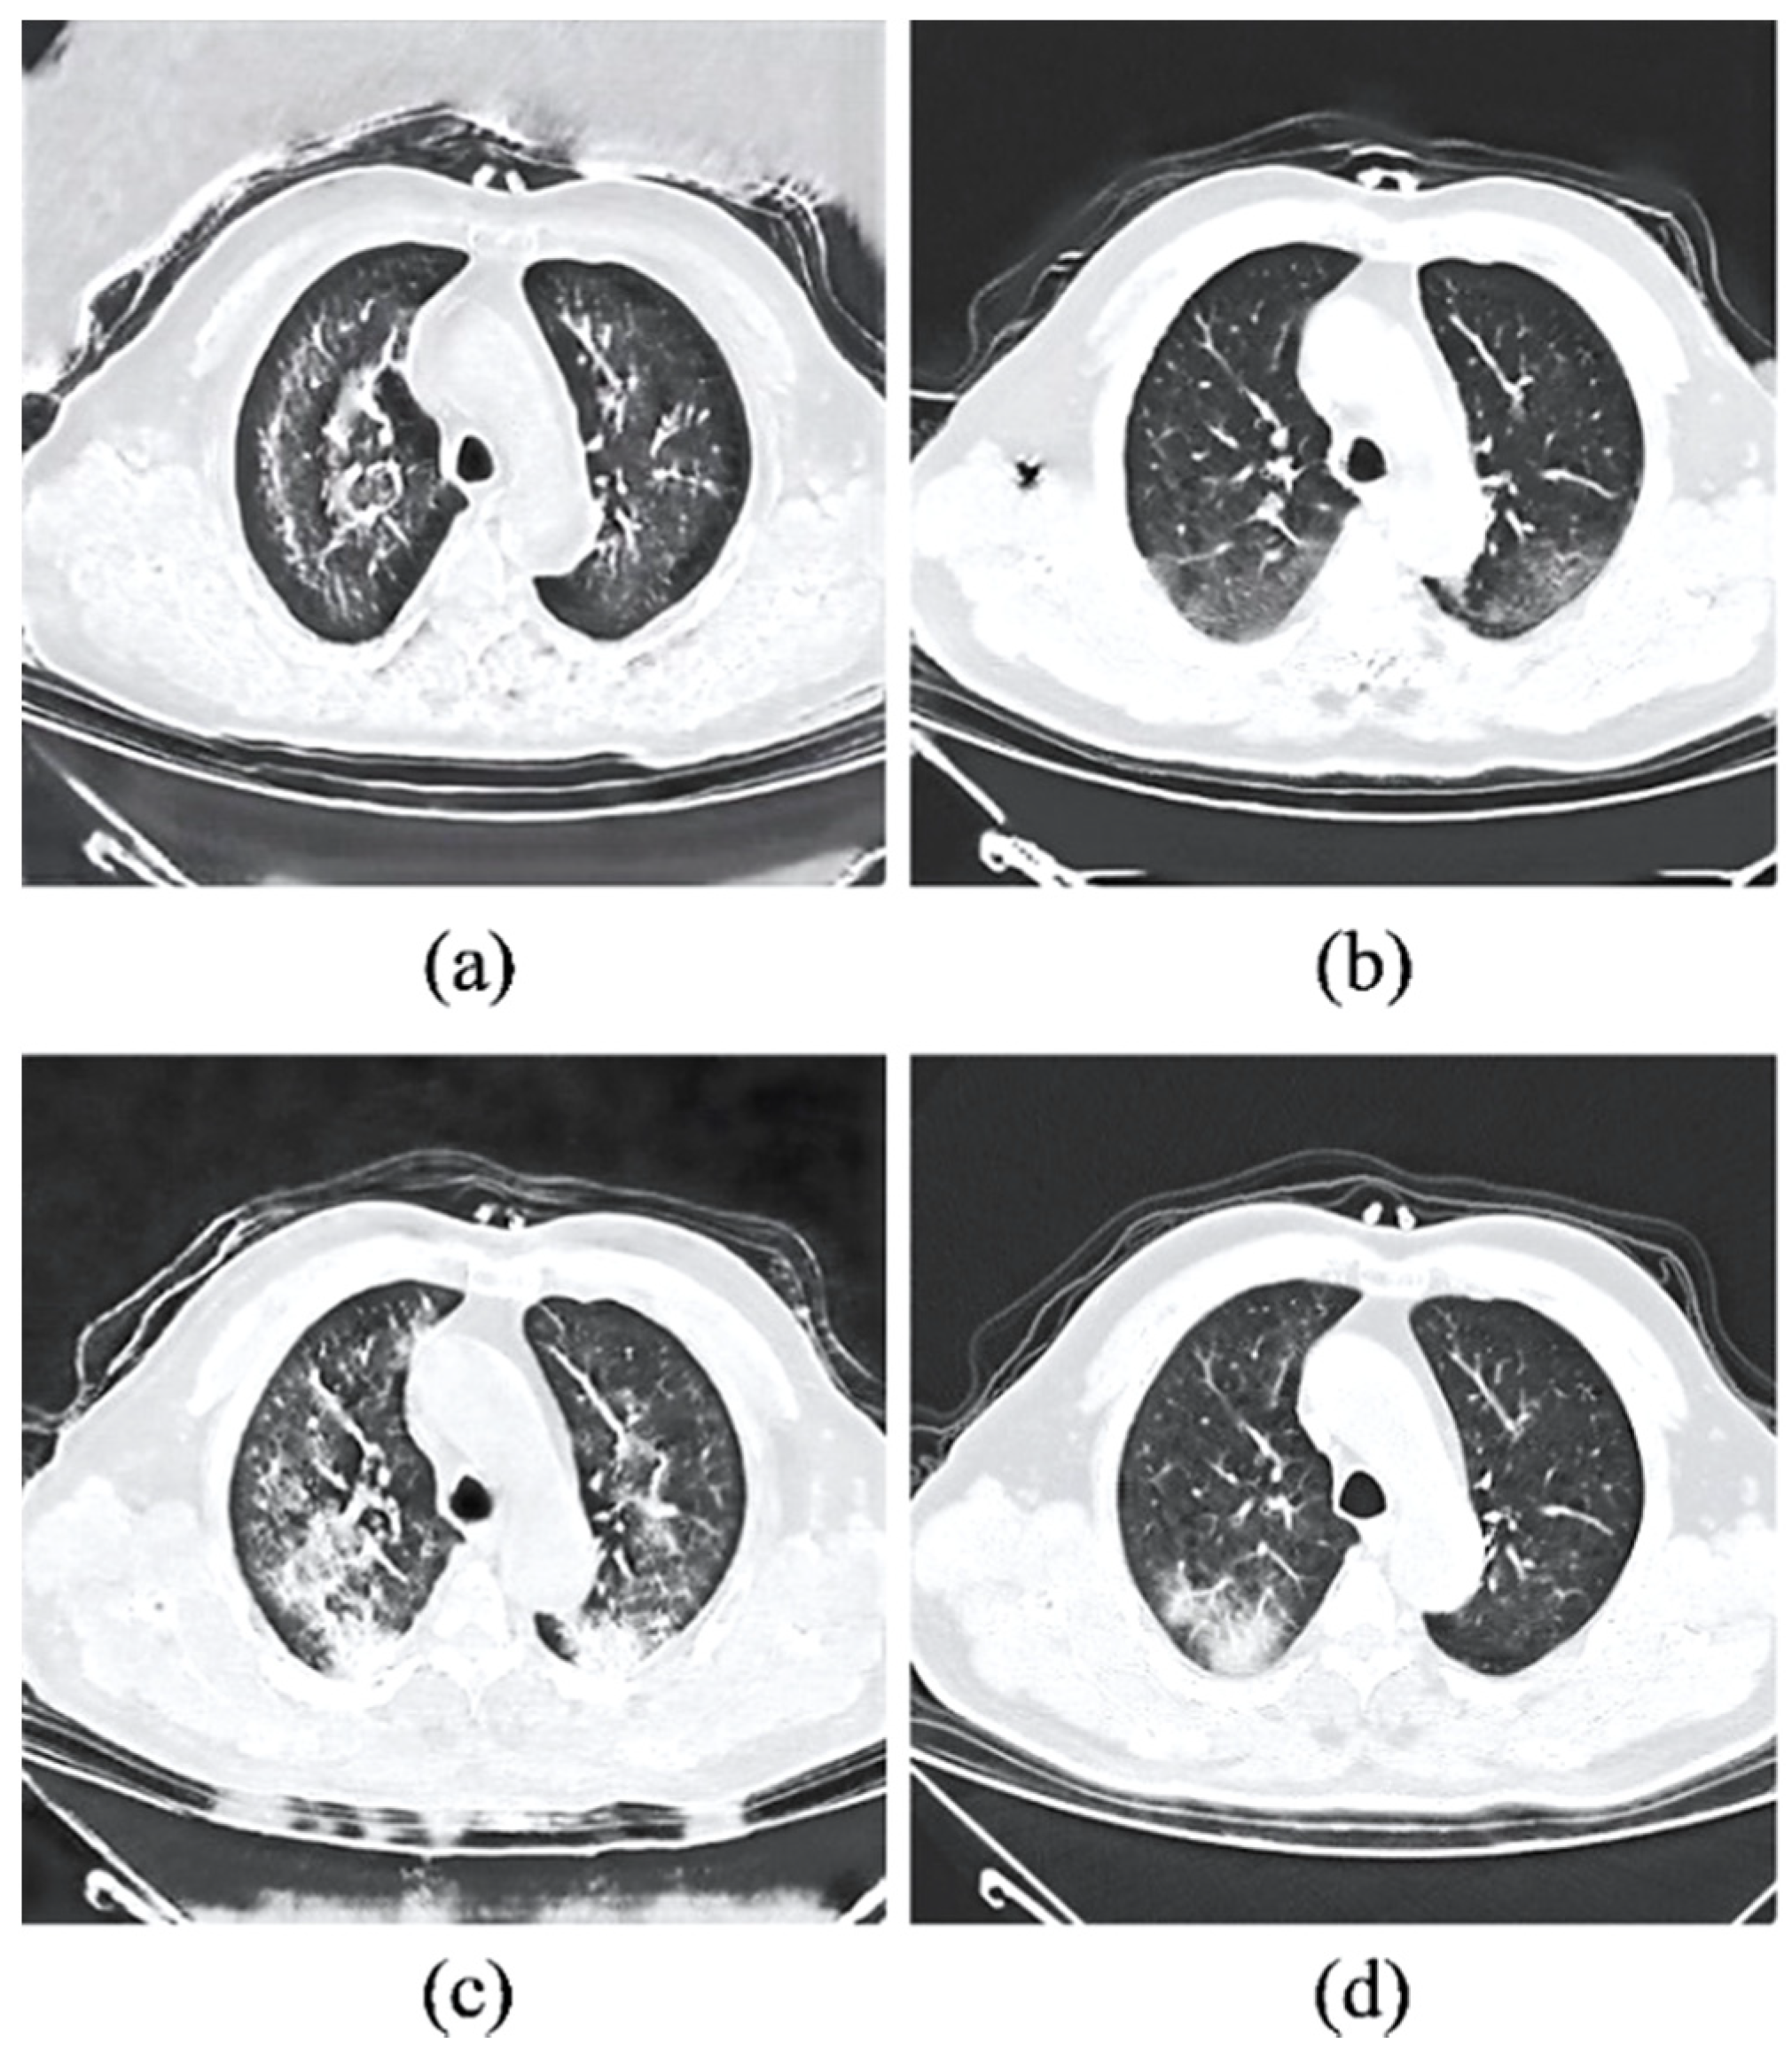

3.3. Qualitative Assessment

3.6. Benchmarking with Existing GANs

3.7. External Validation on Different Clinical Cases

- Perceptual realism and quality. While the perceptual quality can be evaluated using the standard FID metric, the actual reality of the synthetic COVID-19 remains challenging due to the domain knowledge requirement. With the help of an experienced radiologist, the Visual Turing Test reveals a promising result achieved by the synthetic images for generating radiography findings of GGO, which is consistent with the real COVID-19 CT images. Furthermore, exhaustive experiments demonstrate the consistent adversary correlation between image diversity and perceptual quality due to the underlying property of the stacked residual dropout, which induces latent space stochasticity and simultaneously encourages a more unconstrained space of image mapping. Thereby, a larger magnitude of stochasticity can generate additional noise artifacts that could be detrimental to the overall perceptual quality and realism of the images. The impact of the adversarial relationship between perceptual quality and image diversity is addressed by a reduced dropout rate at higher dimensional latent spaces. As a result, drastic improvement in the perceptual quality was noticed without affecting the significance of synthetic features generated on the output images. Furthermore, the sRD-GAN also demonstrated superior performance in terms of perceptual quality compared to other GAN baselines, where images generated from the GAN are distorted by a significant amount of noise artifacts. In contrast, the images generated from CycleGAN and one-to-one CycleGAN models failed to effectively eliminate the noise artifacts.